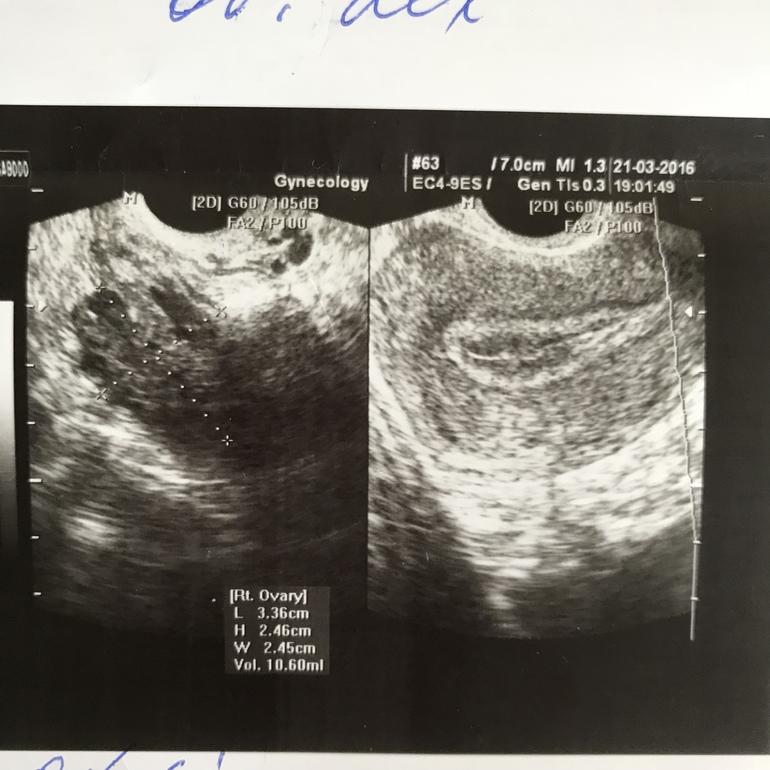

На УЗИ была огромная киста в яичнике, у меня остались все фотки с УЗИ

А матка небеременная

Первое фото это беременность 5 недель 2 дня

Второе фото это 5 недель и 2 дня при кисте

Видно невооруженным взглядом, что ничего похожего на беременность в матке нет на таком же сроке